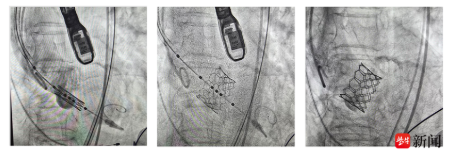

TAVI术中通过股动脉送入介入导管,首先采用球囊对患者重度狭窄的主动脉瓣膜进行预扩张,后将人工主动脉瓣膜送到拟释放位置,精确定位,人工瓣膜顺利释放,替换了原来重度狭窄伴钙化的瓣膜,术中经食道超声确认新的瓣膜位置准确、开放自如,患者主动脉瓣的功能得以恢复,手术成功。

TAVI术中根据瓣膜释放机制与结构有二种方式,一是自膨瓣,通常使用20-22F大鞘,无论是瓣膜硬度、长度及系统的不可调弯性,都会大大增加手术入路并发症的风险;二是球扩瓣,入路仅需14F大鞘,Prizvalve瓣膜的双调弯设计可令过弓、跨瓣等操作更加安全顺畅,适用于本例存在入路极度困难的患者;球扩瓣瓣架偏短,降低阻塞冠脉和对传导束压迫的风险,减少了TAVI术后冠脉闭塞和植入永久起搏器的几率。但该瓣膜的操作需精确定位,术者与助手要实现精细配合,且瓣膜为一次释放,无法回收。